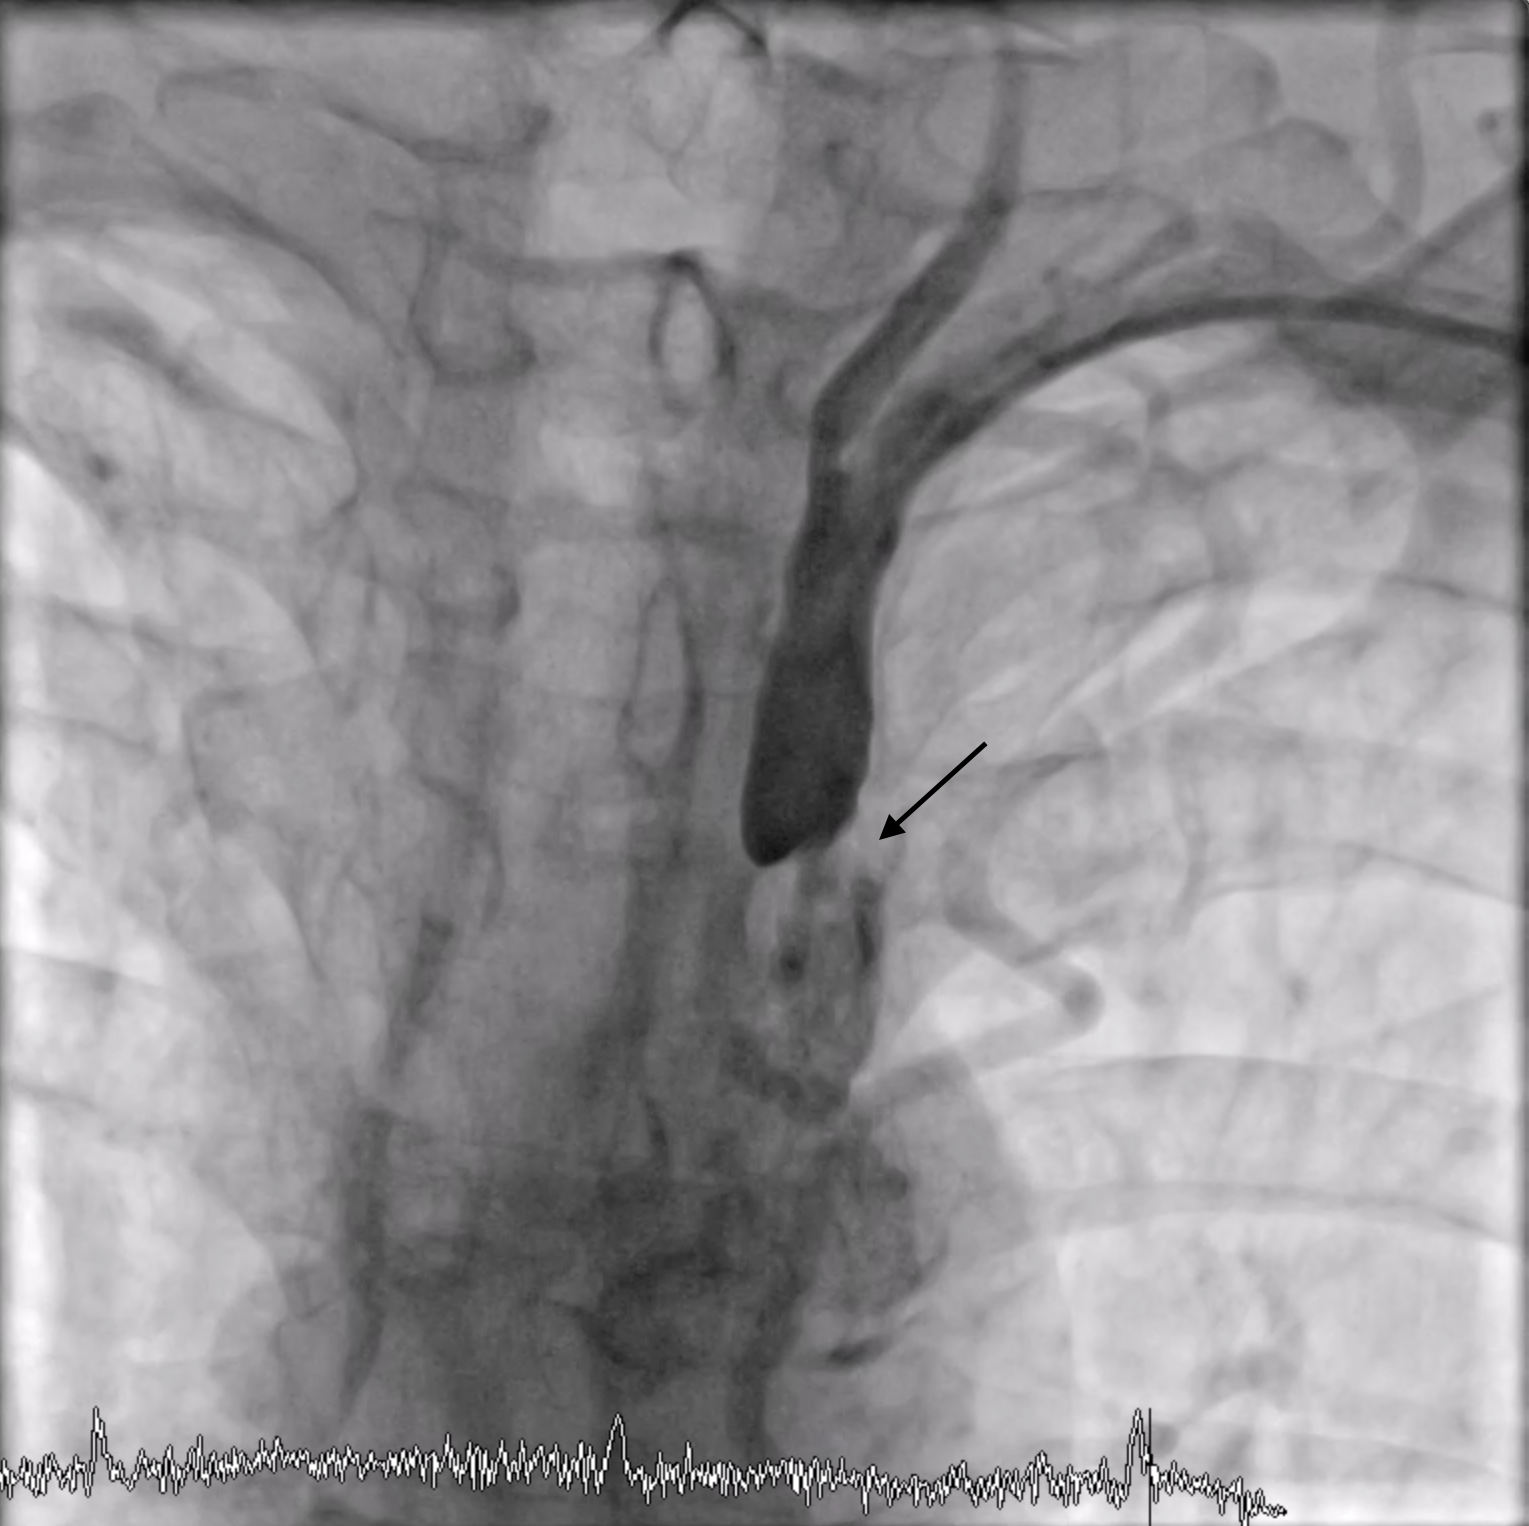

The subclavian angiography was performed by left radial approach (6 Fr sheath) and using a diagnostic catheter JR 4.0. There was 90% stenosis of the left subclavian artery near the aortic arch (black arrow).

Stenosis subclavian.png